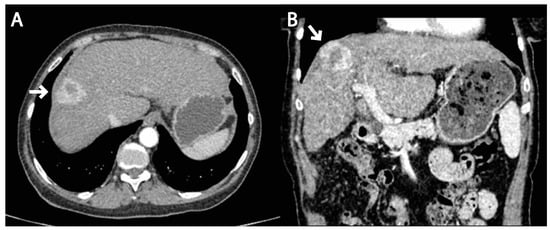

2. Case Report